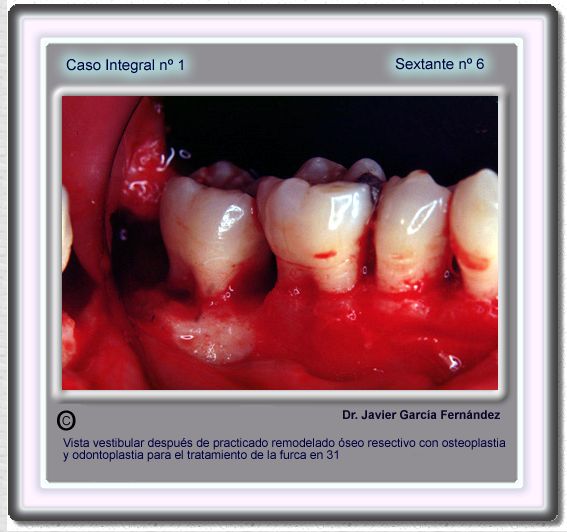

image 106